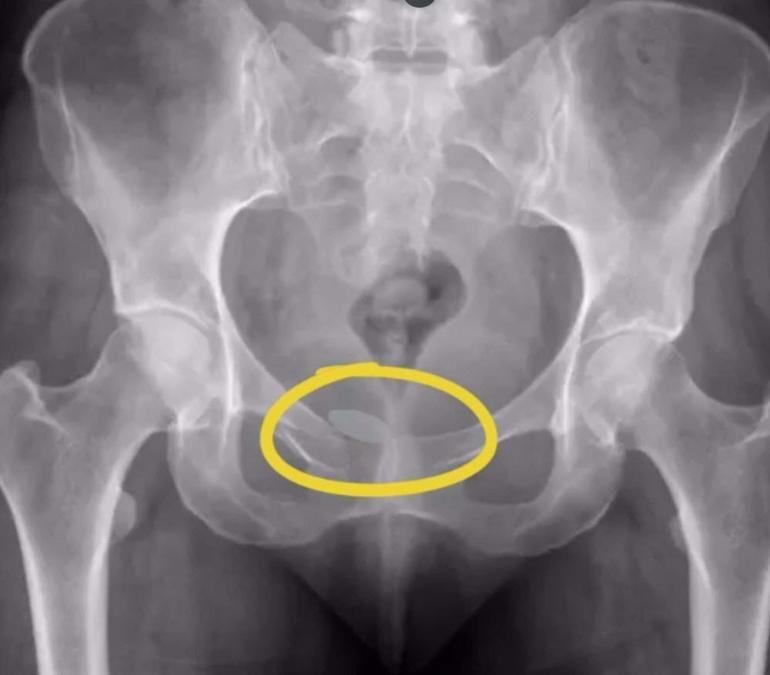

İl Emniyet Müdürlüğü Narkotik Suçlarla Mücadele Şube Müdürlüğü ekipleri, istihbarat çalışması ile yurt dışından İzmir'e uyuşturucu getirileceğini bilgisine ulaştı. İzmir Adnan Menderes Havalimanı'nda, 9 Ekim'de önlem alan ekipler, tespit edilen 2'si Alman uyruklu 5 şüpheliyi durdurdu. Şüphelilerin yapılan iç beden muayenesinde, prezervatifler içinde yutulmuş ve vücut boşluklarına gizlenmiş halde 21,19 gram eroin, 12,70 gram kokain, 7,76 gram metamfetamin ve 7 sentetik hap ele geçirildi. Gözaltına alınan şüpheliler, dün adliyeye sevk edildi. Şüphelilerden Almanya vatandaşı A.D.M. ve F.M. tutuklandı, diğerleri adli kontrol şartıyla serbest bırakıldı.